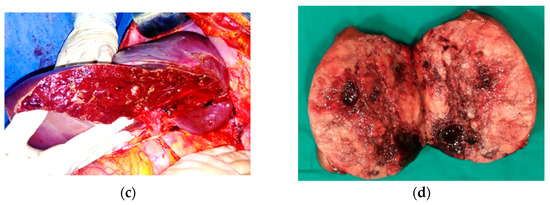

The case was discussed in a multidisciplinary setting, and debulking liver resection involving the resection of the two large groups of metastases in a two-stage approach was recommended. The first-stage surgery removed the left metastatic group by means of an echo-guided non-anatomical resection of segment 2, extended to segment 3 and 4 superior, along with the invaded left hepatic vein (Figure 5). The operative time was 240 min, and blood loss was 750 mL, necessitating 1 MER transfusion. At histologic examination, GIST liver metastases were confirmed, with a mitotic count of less than 5/50 HPF and a Ki-67 Index of 10%, DOG1 positive, and CD117 positive. Postoperative transient mild liver insufficiency was encountered on postoperative day (POD) 4 and lasted until POD 12 (maximum total bilirubinemia = 3.7 mg/dl, INR = 1.74)—Grade A according to ISGLS criteria, elevated cytolysis (AST = 298, ALT = 528), and ascites (maximum 1000 mL/day), with no clinical alterations. In addition, transient fever and leukocytosis was recorded on PODs 10 to 17. The patient was discharged on POD 24 in good condition.

Figure 5.

First-stage surgery. Aspect of the liver: (a) prior to first-stage resection; (b,c) after resection; (d) resected specimen.